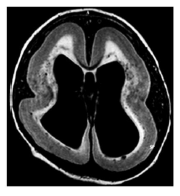

A lissencefalia completa ou agiria consiste em um cérebro liso com córtex espesso, sem giros ou sulcos secundários. Pode ocorrer isoladamente ou fazer parte da síndrome de

Provas